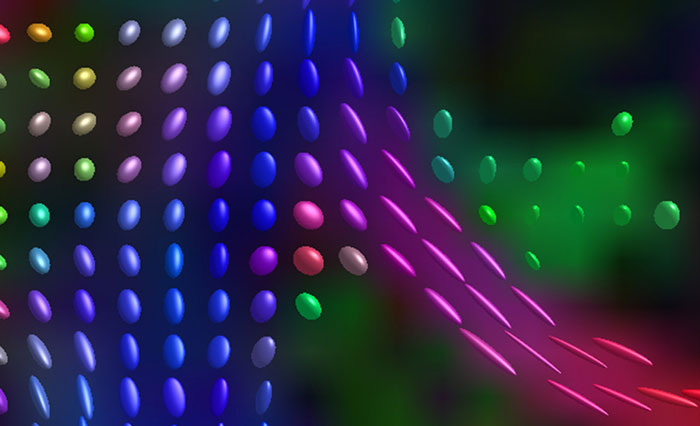

Advancing diffusion MRI

These images are produced using the ABCD protocol and illustrate the use of more sophisticated and accurate models of diffusion. The color FA maps are shown for reference. The diffusion tensor model represents the diffusion within each voxel as an ellipsoid.

Alternative models, such as constrained spherical deconvolution, better capture the rich information available with the use of high b-value dMRI and many sampling directions. In much of the brain, voxels contain multiple white matter tracts, and it is essential to capture this information to be able to perform accurate tractography and generate diffusion connectomes.

Diffusion acquisition on Achieva 3.0T dStream with matrix 140x141, 81 slices, FOV 240x240 mm, voxels 1.7x1.7x1.7 mm, TR 5300 ms, TE 89 ms, flip angle 78, MultiBand SENSE factor 3, partial Fourier 0.645, 102 diffusion directions, b-values 0 (6), 500 (6), 1000 (15), 2000 (15), 3000 (60) , scan time 2x 4:37 min. Images provided by Dr. Watts.